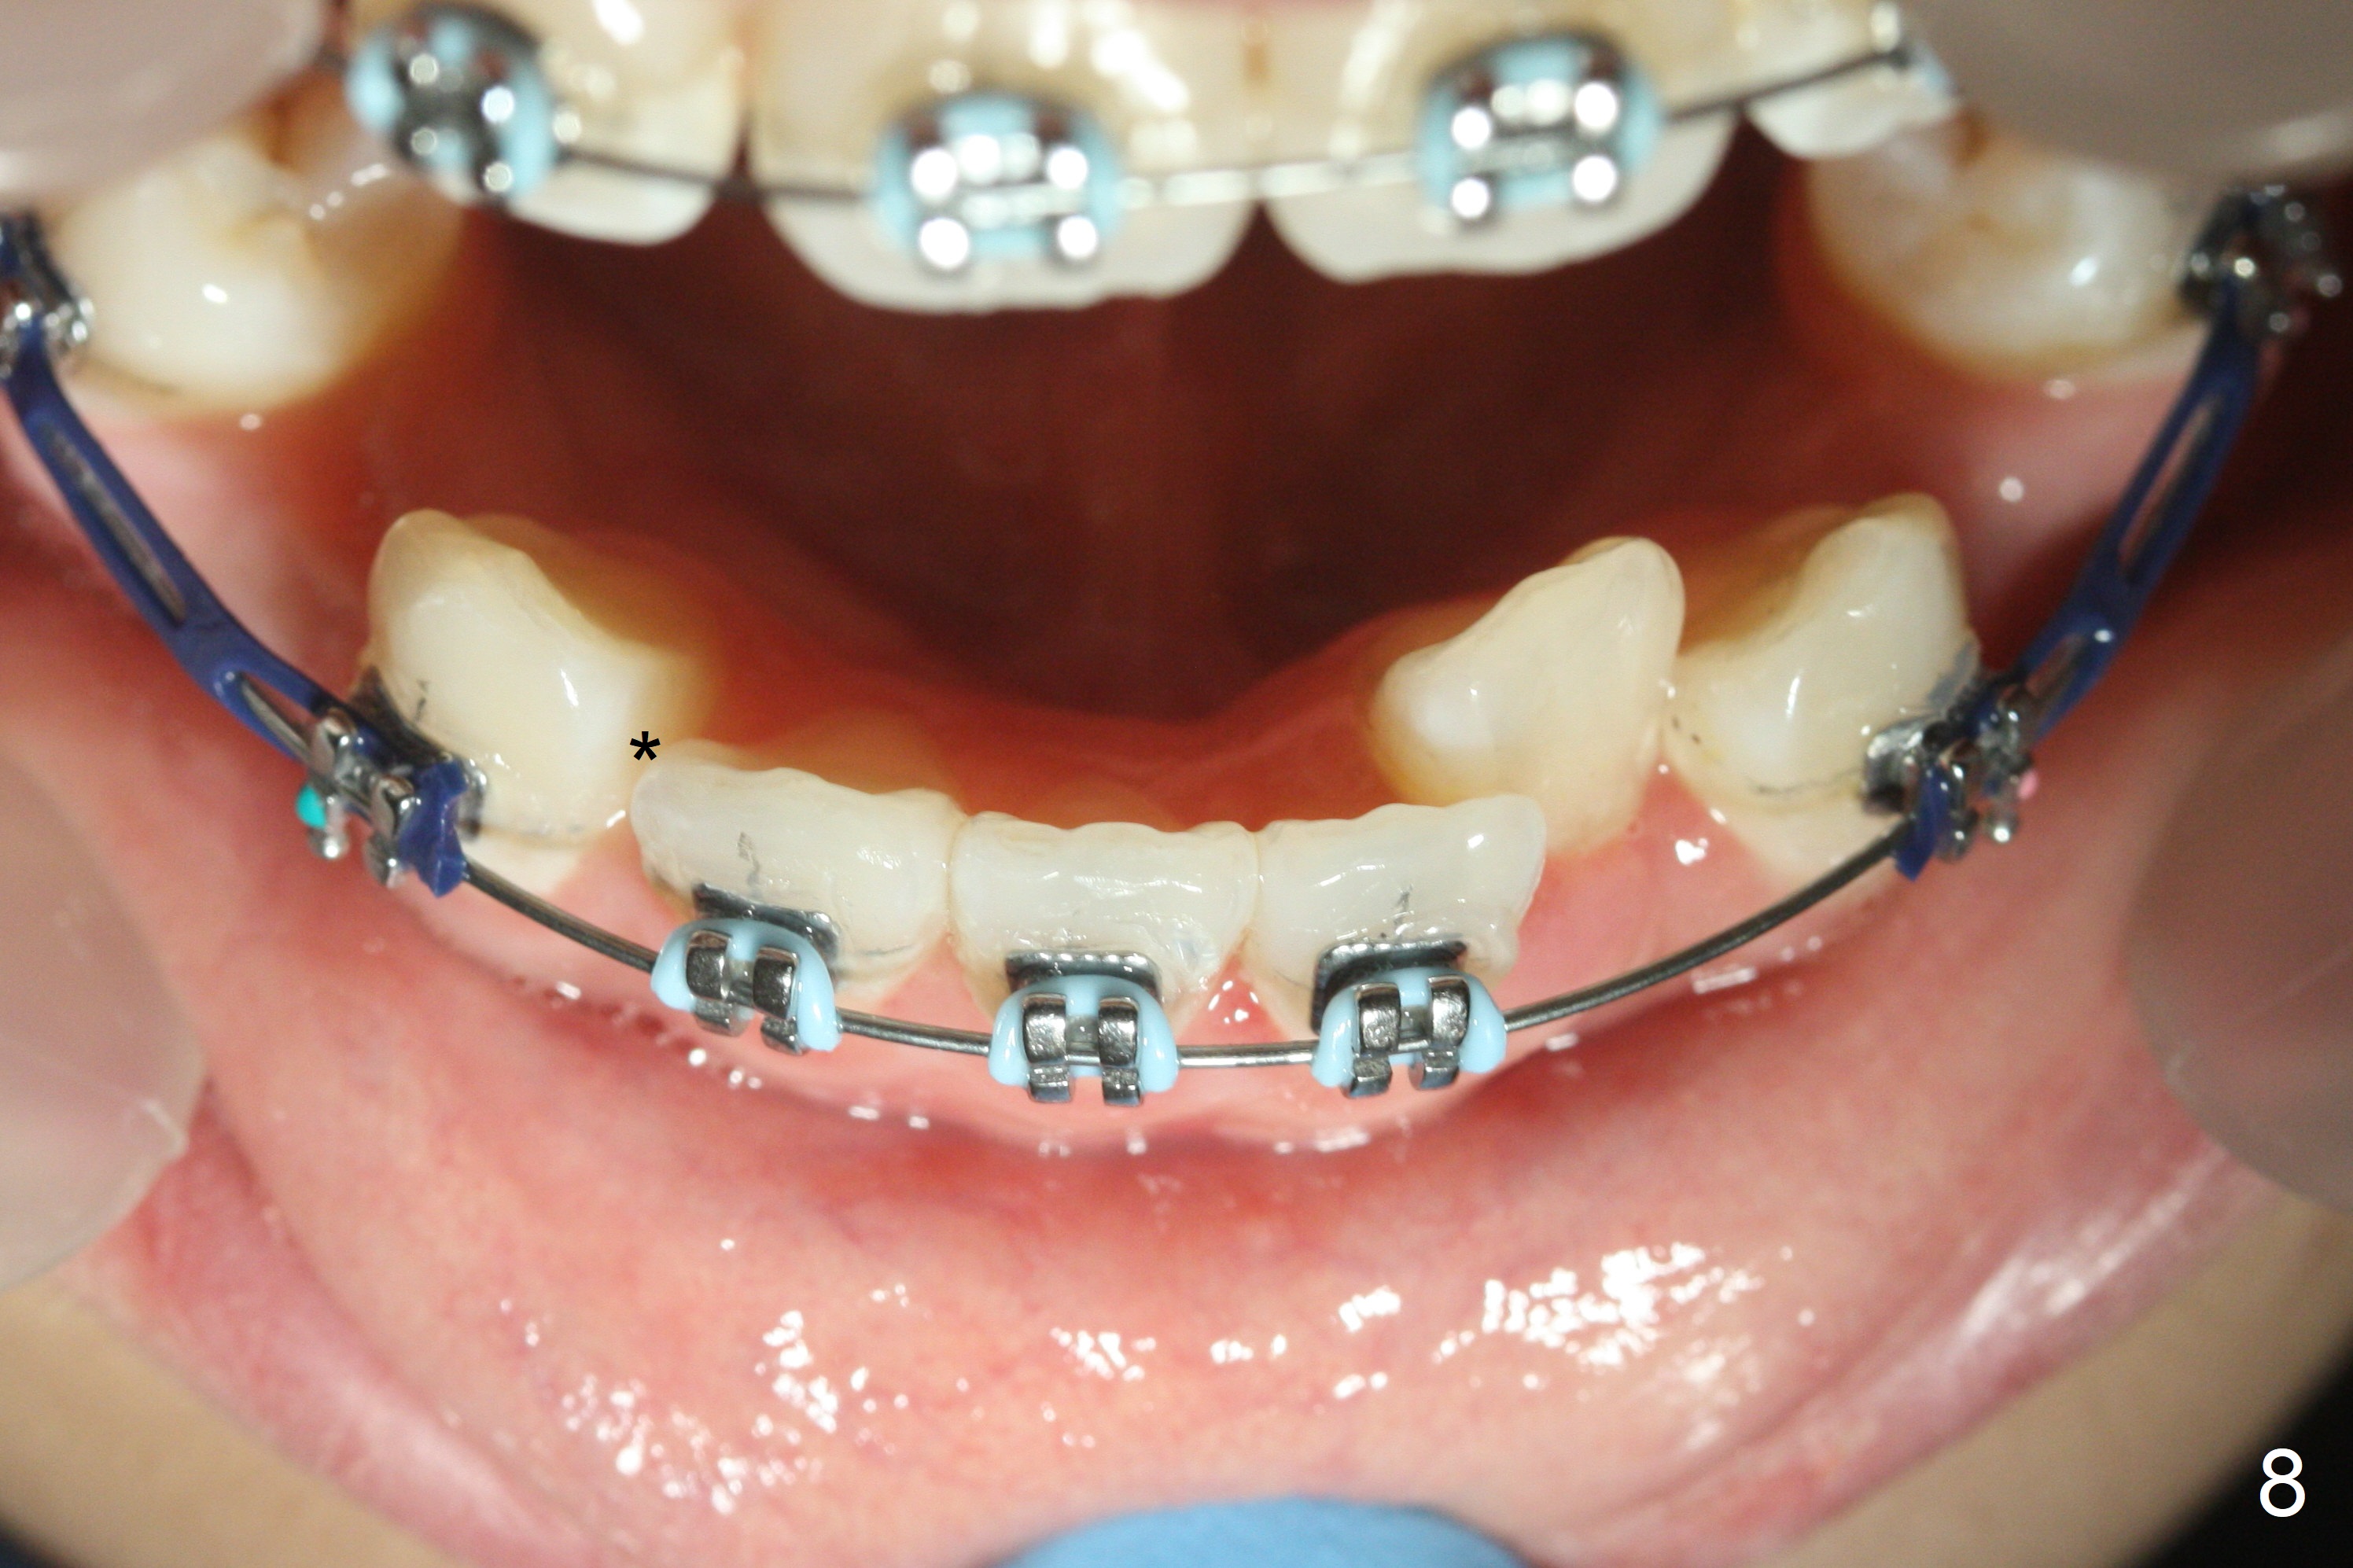

Nearly 3 months post extraction, UL 3 (Fig.7 arrow), LR 3 (Fig.8 *) and UR 3 have distalized by themselves. After changing 16 niti wires, power chains x 4 are placed between 3 and 6 (Fig.7,8) to lay foundation to reduce upper anterior overjet and lower crowding (including LL2 linguoversion). When the space between LR 2 and 3 increases (Fig. 8 *), it will be easy to shift the lower midline (Fig.5) to the right as an open coil spring will be placed between LL 1 and 3. Check the facial and dental midlines next visit before removing the wires.